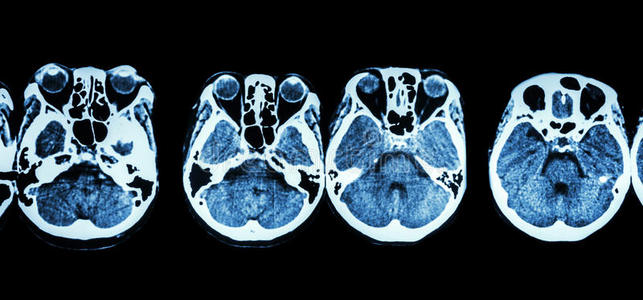

脑和颅底ct扫描(显示眼,筛窦,小脑,大脑等结构)照片